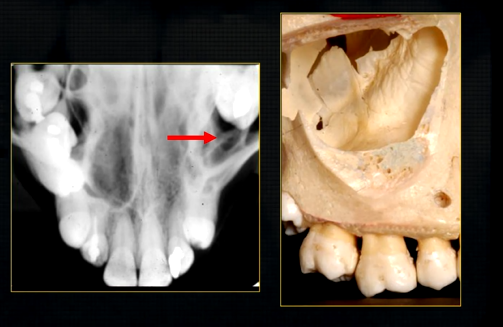

dental radiographic images are 2D representations of the 3D teeth and bones of the skull

it is important that you are aware of the whole skull but particularly the maxilla and the mandible

the upper jaw - the maxilla - what is circled in red?

the nasal cavity

what is seen here?

the nasal septum and the inferior nasal concha

what is the bottom arrow showing?

the floor of the nose - just above the apices of the upper anterior teeth

what can you say about the surface anatomy of the maxilla around the teeth themselves?

very undulating - prominences over roots

bony spike of the anterior nasal spine

becomes visible at the side view